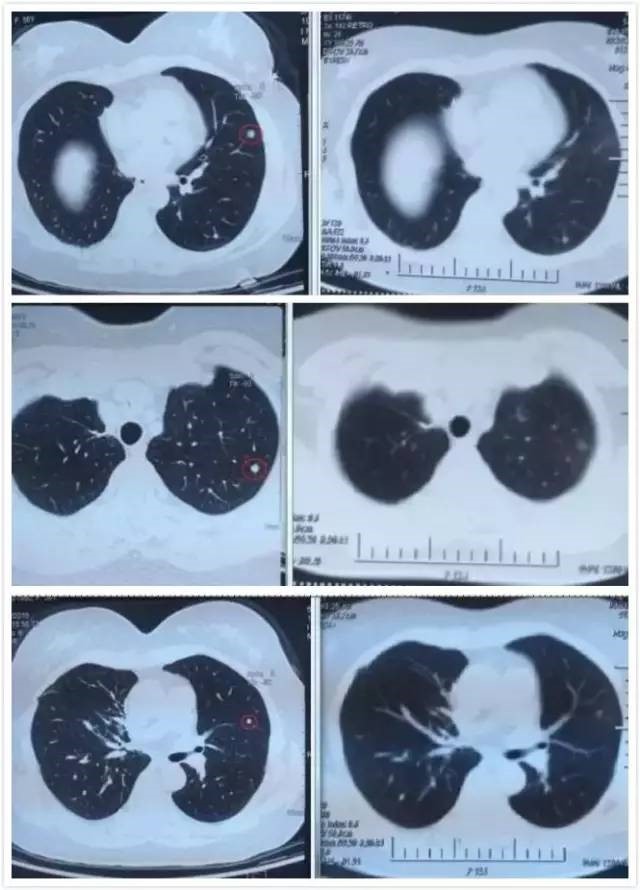

A45治疗技术临床案例--肺癌

案例一

患者女性,50岁。肺腺癌。

2015年1月确诊为肺腺癌,射频消融术辅助化疗四周期,同年7月,肿瘤复发并出现肾脏转移,经过细胞免疫治疗未见好转。2016年5月,经过A45首席专家会诊,制定治疗方案,患者接受A45治疗一个疗程,肺部的三个病灶全部消退。目前患者状态良好。